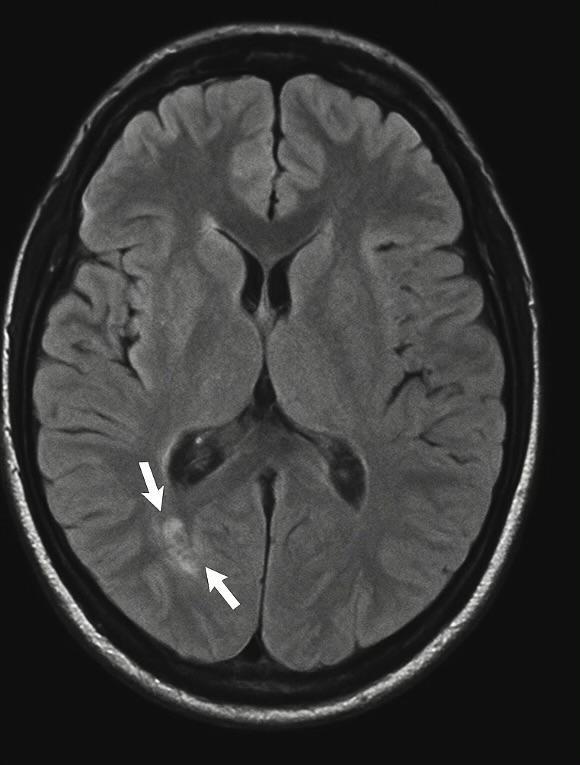

Electroencephalogram (EEG) demonstrated diffuse slowing with intermittent delta brush patterns, consistent with autoimmune encephalitis. The brain MRI was unremarkable, a finding commonly seen in early-stage disease (Figure 1).